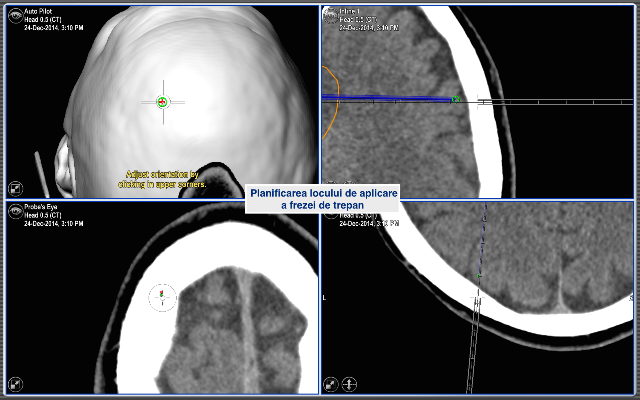

Toate aceste incomodități lipsesc în cadrul biopsiei cu utilizarea neuronavigației fără cadru stereotaxic. Astfel, procedura pentru pacient arată cât se poate de simplu. Pacientul intră în sala de operație fără cadru pe cap și iese de acolo cu procedura de biopsie realizată, localizarea și precizia biopsiei fiind confirmate pe masa de operație.

Pacientul S., a beneficiat de tehnologiile existente în volum deplin. Operația a durat 2 ore. Pacientul și-a revenit după o oră de la intervenția chirurgicală, iar peste o zi a fost externat. Pentru prelevarea biopsiei a fost aleasă o porțiune de tumoare localizată la adâncimea de 13 cm de la suprafață. Locul ales a fost țintit cu precizia de 0,2mm! Acest grad de precizie este suficient pentru toate biopsiile cerebrale, iar în anumite circumstanțe, sistemul poate fi utilizat și pentru tratamentul parkinsonismului.